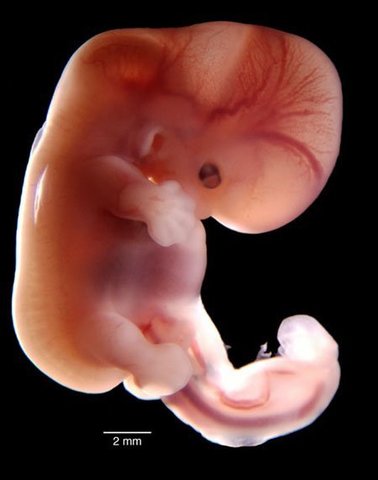

Período de transición entre la formación del embrión (embriogénesis) y la de los órganos (organogénesis) del futuro bebé. Los primeros latidos cardíacos se manifiestan hacia el 23.º día. El embrión adquiere su forma definitiva:El embrión flota en medio de la cavidad amniótica, unido a la parte externa del huevo por el cordón umbilical, que se está formando. Al final de este primer mes, el embrión mide 5 mm.

• Segundo mes 5 .a- 6 .a Semana

Segundo mes 5 .a- 6 .a Semana

Del embrión al feto. 5.a-6.a semanas Se forman los dientes. El corazón se ha hecho tan grande que forma una pequeña protuberancia; se dibujan las cuatro cavidades cardíacas. Se desarrollan el estómago, el intestino, el páncreas y el aparato urinario.